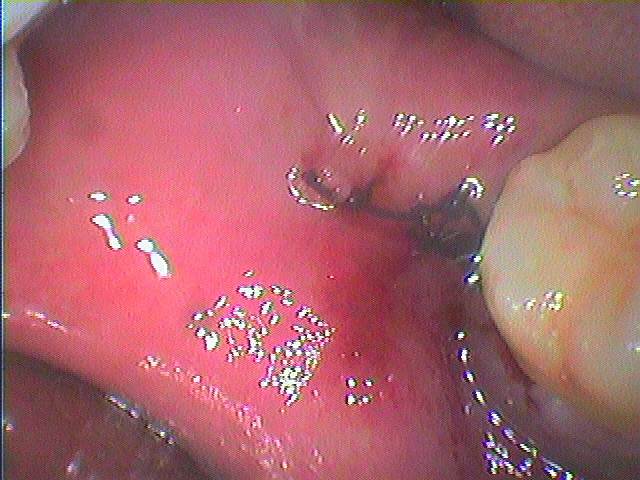

根がずいぶん曲がっていました

抜歯窩になります

縫合して終了となります